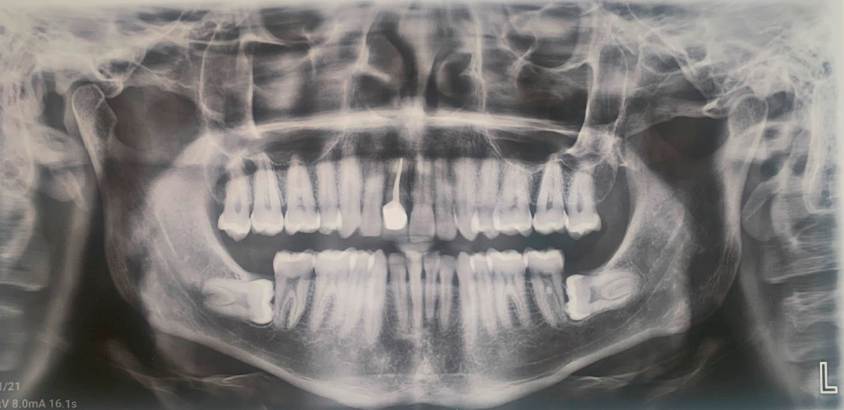

At the end of orthodontic treatment, fixed appliances were removed and retainers were placed. In panoramic radiographs and lateral head films, the periodontal and endodontic health of the transplanted tooth can be identified, as well as the root integrity.

In this case, no occlusal changes were found and the irregularity index was 2 mm in the lower arch 12 years after the end of treatment. Class I relationships were achieved in molars and canines on both sides; the overjet and overbite were ideal. Long-term follow-up (12 years) of the transplanted tooth at the # 11 tooth site has remained stable and functional (Figure 6). The root of the transplanted tooth was found to have deficient cortical bone at the beginning of the treatment, so light forces were used throughout the treatment to avoid root resorption and to obtain maximum stability (Figure 7).

The cephalometric values for pre-treatment, post-treatment, and cephalometric evaluation 12 years after orthodontic treatment are shown in Table 1. Superimpositions between the three cephalometric tracings show changes in cephalometric measurements at the beginning of T1, T2, and T3. The post-treatment cephalometric analysis highlights the dental effects, with retroclination of the upper arch and lower incisors, and an increase in the interincisal angle. In the 12-year after treatment evaluation, no changes were observed in the position of the upper and lower incisors (Figure 8).